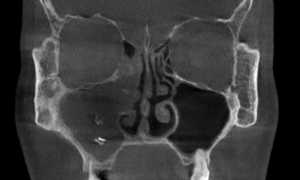

- Гайморит.

Внимание! Острый фарингит наиболее часто сопровождается риносинуситом – слизь, стекающая в гортань, раздражает слизистую оболочку глотки, вызывая сильную боль.

Воспалительный процесс локализуется в одном отделе глотки, поэтому выделяют три формы заболевания – назофарингит, мезофарингит и гипофарингит. Но в некоторых случаях определение локализации затрудняется из-за выраженной гиперемии и отека слизистой оболочки.